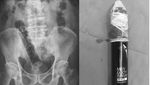

Pria 50 tahun datang ke IGD dengan dumbell 5 pon (2,2 kg) tersangkut di rektum. Setelah prosedur sedasi dan manuver khusus, barbel berhasil dikeluarkan dan pasien pulang dengan kondisi baik. (Foto: Cureus Journal)